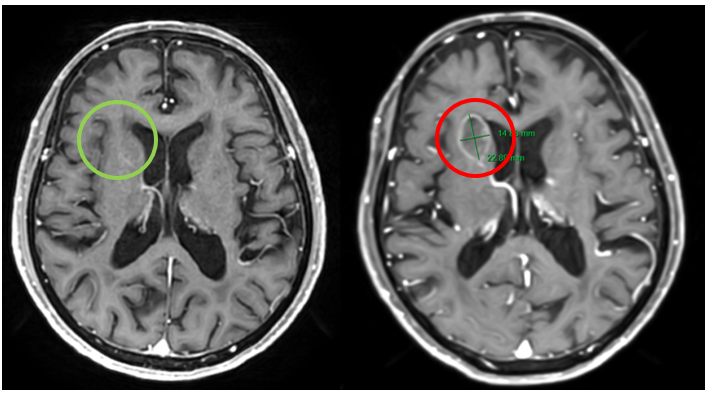

Hình 8. Hình ảnh não không có khối choán chỗ trong thời gian điều trị (mũi tên xanh) và não xuất hiện khối u di căn não thùy trán phải cạnh sừng trán não thất bên, kích thước 14x22 mm sau khi bỏ điều trị 3 tháng (mũi tên đỏ), trên phim cộng hưởng từ sọ não tại mặt phẳng axial.